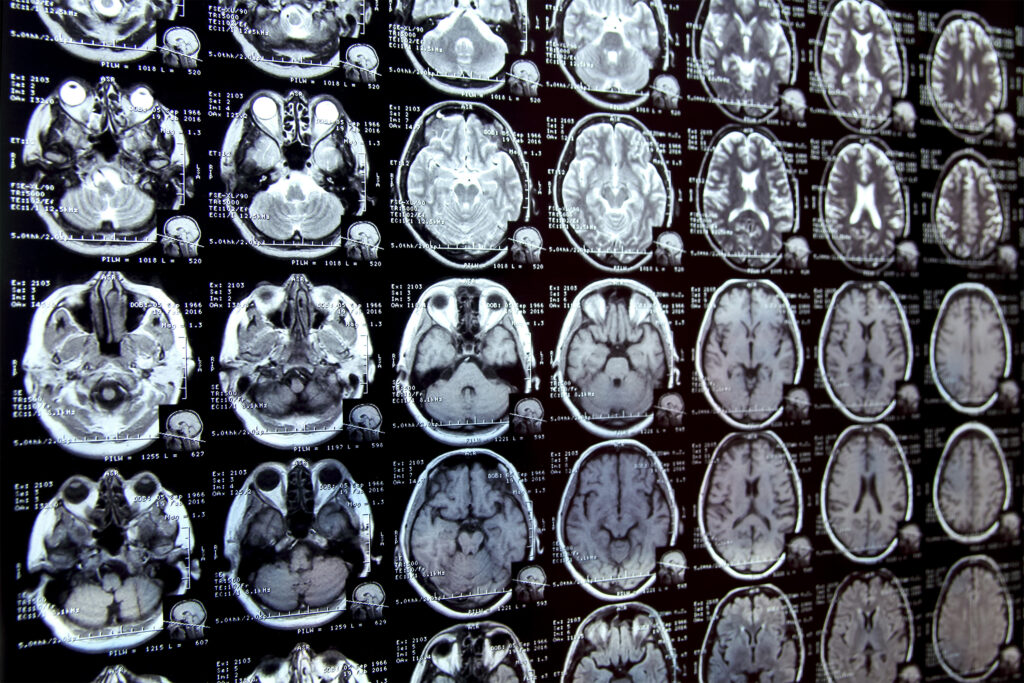

Annotating regions of interest in medical images, a process known as segmentation, is often one of the first steps clinical researchers take when running a new study involving biomedical images.

For instance, to determine how the size of the brain’s hippocampus changes as patients age, the scientist first outlines each hippocampus in a series of brain scans. For many structures and image types, this is often a manual process that can be extremely time-consuming, especially if the regions being studied are challenging to delineate.

To streamline the process, MIT researchers developed an artificial intelligence-based system that enables a researcher to rapidly segment new biomedical imaging datasets by clicking, scribbling, and drawing boxes on the images. This new AI model uses these interactions to predict the segmentation.

This new system, MultiverSeg, combines the best of each approach. It predicts a segmentation for a new image based on user interactions, like scribbles, but also keeps each segmented image in a context set that it refers to later.